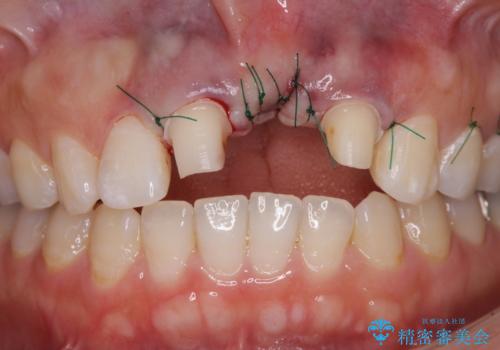

欠損部の歯肉が窪んでいるため、歯肉移植により形態を改善し、オールセラミックブリッジにて補綴することとしました。

- 外科手術のため、術後に痛みや腫れ、違和感を伴います

- 歯周組織再生治療は患者様の状態によって術後の経過が異なります(見た目が改善しない場合もあります)